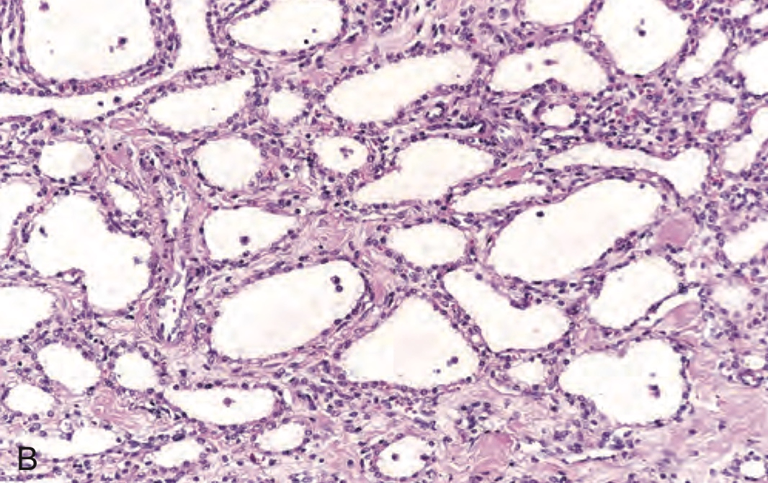

• Serous cystic neoplasm는 주로 췌장의 꼬리에서 장액성분을 함유하는 작은 (1-3mm) 낭종이 solitary 또는 multiple하게 생기는 질병이다. 보통 외과적 치료로 해결되며 악성으로 진행하는 경우는 매우 드물다. VHL tumor suppressor gene의 loss of function과 높은 연관성을 보인다. 조직소견으로는 cuboid epithelial lining의 점액이 관찰된다.

Pathologic Basis of Disease, Robbins Pathology, 10th edition (pg 889)